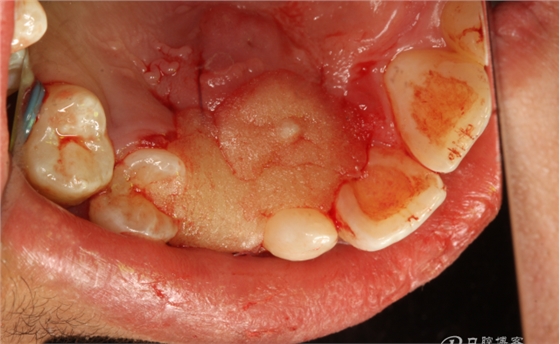

圖13.上牙周塞治劑,兩周后復(fù)診。